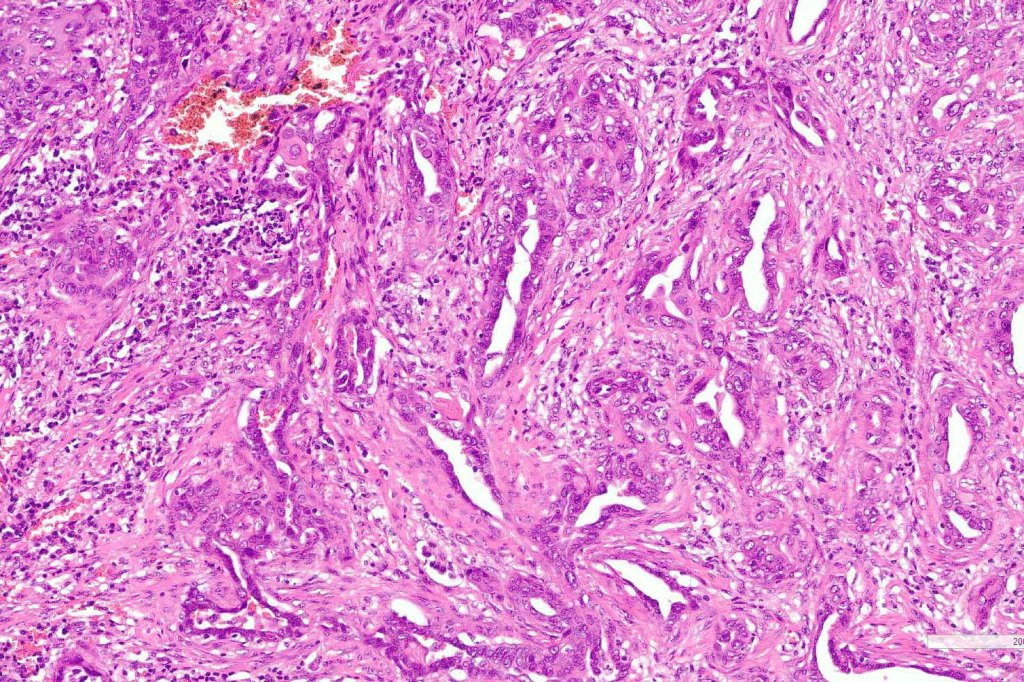

•Ulceration and solar elastosis are common

•Widely infiltrating biphasic tumor

•Adenocarcinoma in deeper reaches

•Deep part may show both ducts and glands

•Often extends to the subcutaneous fat

•Perineural infiltration is commonly seen